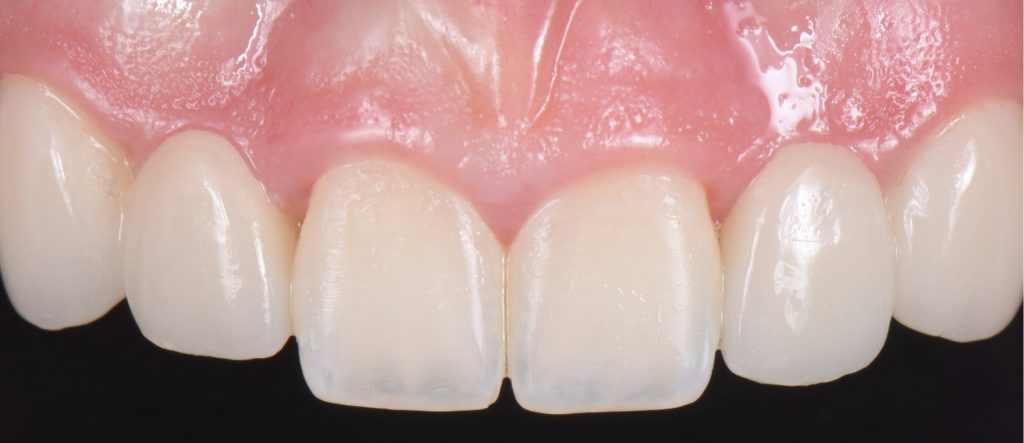

Solution #2: Resin-Bonded Fixed Dental Prostheses (RBFDP)

RBFDP is a proven solution for congenitally missing lateral incisors (Figs. 2-12). Although it is considered an interim restoration, the literature provides substantial evidence supporting its long-term potential. However, the clinical performance of an RBFDP is significantly superior to that of a bilateral retainer, and the dissimilar mobility of the abutment teeth explains this.

When placing an RBFDP from a central incisor to a canine, each abutment wants to move under occlusal load, but because of the position each tooth occupies in the arch, loading occurs in different vectors, therefore, leading to debonding of the retainer of the abutment tooth with the least mobility. When considering which one of the adjacent teeth will work best as the abutment, the clinician needs to evaluate:

From an occlusal standpoint, patients with shallow overbites or a large amount of overjet make better candidates for RBFDP, and the pontics should be avoided in all lateral excursions, including crossover.

Space requirements and connector dimensions depend on material selection. Utilizing zirconia has been proven to be more predictable over time, and recommended connector dimensions are:

The amount of tooth reduction is based on available interocclusal space, and often, there is enough space requiring minimal preparation. The key is to stay in enamel. It is also advisable to stay 2.0 mm away from the incisal edge so that the zirconia retainer does not affect the translucency of the natural tooth.